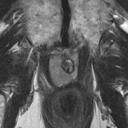

We present a novel technique to discover and exploit weak causal signals directly from images via neural networks for classification purposes. This way, we model how the presence of a feature in one part of the image affects the appearance of another feature in a different part of the image. Our method consists of a convolutional neural network backbone and a causality-factors extractor module, which computes weights to enhance each feature map according to its causal influence in the scene. We developed different architecture variants and empirically evaluated all of our models on two public datasets of prostate MRI images and breast histopathology slides for cancer diagnosis. To confirm our quantitative results, we conduct ablation studies and investigate the explainability of our models via class activation maps. Our findings show that our lightweight block extracts meaningful information and improves the overall classification, together with producing more robust predictions that focus on relevant parts of the image. That is crucial in medical imaging, where accurate and reliable classifications are essential for effective diagnosis and treatment planning.